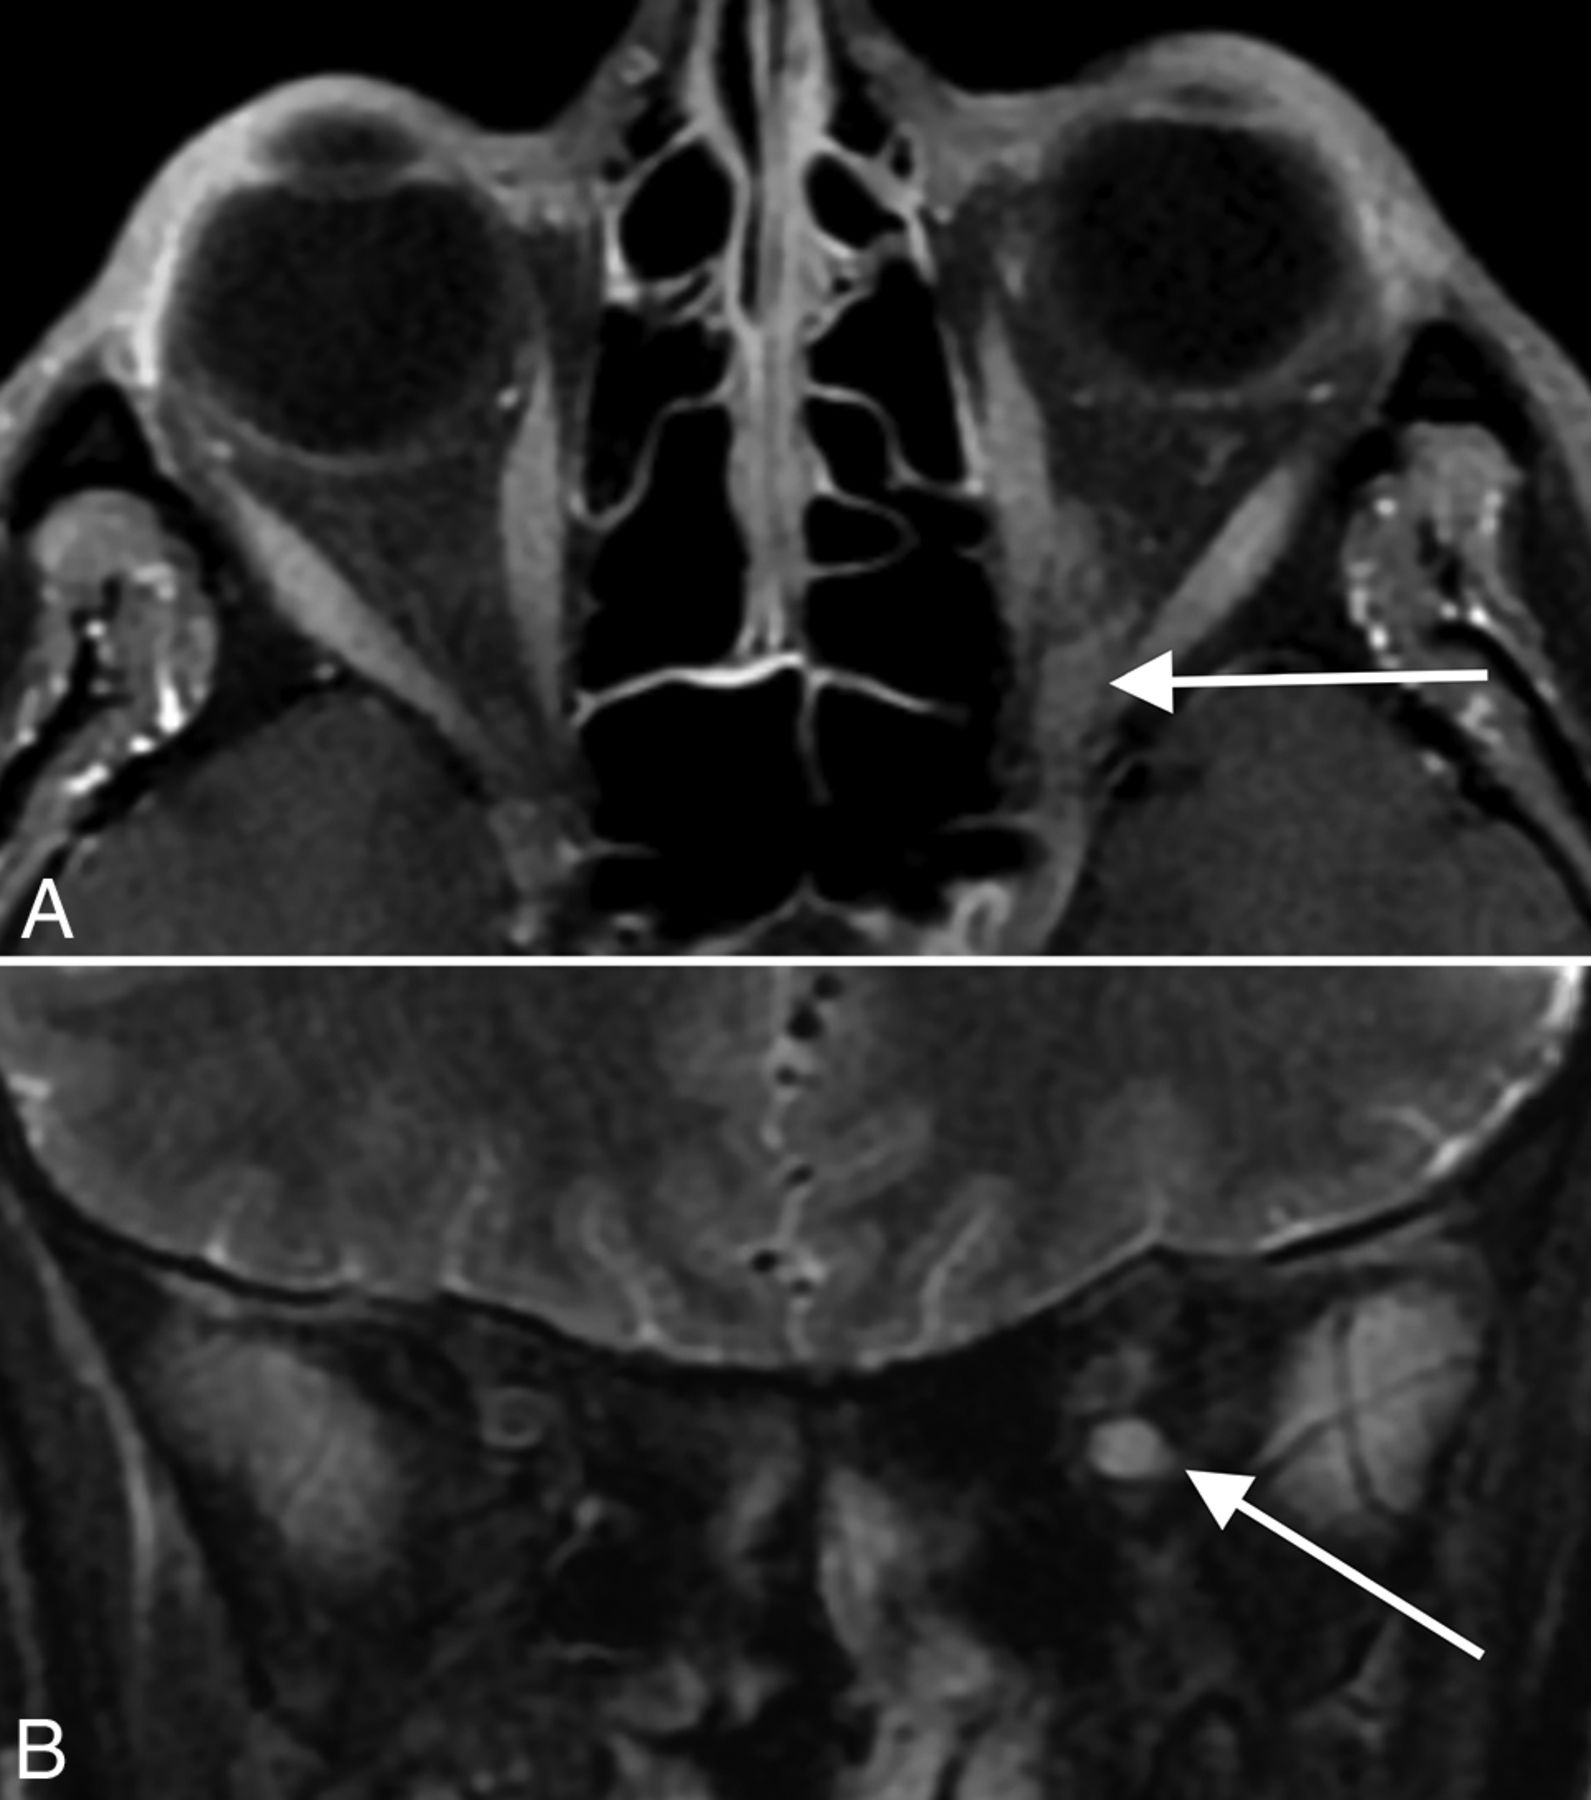

Stroke. A 53-year-old man with COVID-19 with an axial CTA image (A) demonstrating an abrupt cutoff of the proximal M1 segment of the left MCA (arrow), consistent with thrombosis. The patient later underwent MR imaging, with a DWI sequence (B) demonstrating acute infarctions in the left MCA territory (arrows). An 85-year-old woman with COVID-19 and MR imaging with a DWI sequence (C and D) demonstrating acute infarctions in both the anterior (arrow, C) and posterior (arrows, D) circulations, consistent with central embolic etiology. Most patients in our cohort had stroke of either embolic or cryptogenic etiology.